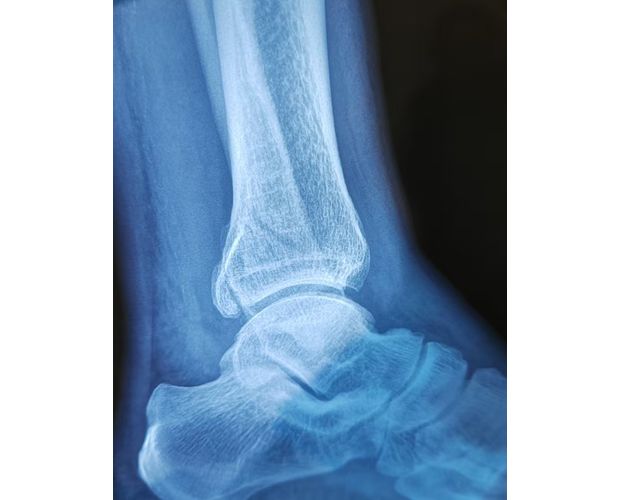

2月4日,何店鎮(zhèn)中心衛(wèi)生院接診一名左踝關(guān)節(jié)外傷患者,經(jīng)影像檢查,確診為左脛、腓骨下段骨折。外科醫(yī)生姜穩(wěn)迅速完成術(shù)前檢查及病情評估,并與患者及家屬深入溝通治療方案。在患者強烈要求于本院進行手術(shù)的情況下,為最大限度保障手術(shù)質(zhì)量與安全,該院特邀請醫(yī)共體牽頭單位——曾都區(qū)人民醫(yī)院脊柱創(chuàng)傷外科專家團隊前來指導(dǎo)。